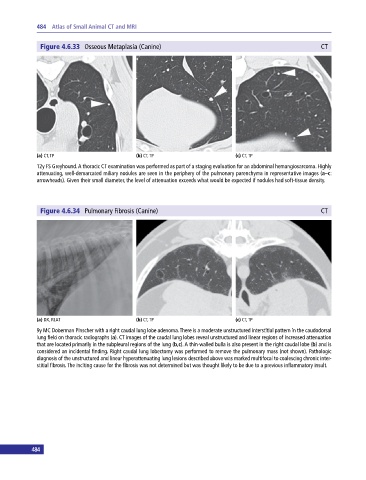

Figure 4.6.33 Osseous Metaplasia (Canine) CT

(a) CT, TP (b) CT, TP (c) CT, TP

12y FS Greyhound. A thoracic CT examination was performed as part of a staging evaluation for an abdominal hemangiosarcoma. Highly

attenuating, well‐demarcated miliary nodules are seen in the periphery of the pulmonary parenchyma in representative images (a–c:

arrowheads). Given their small diameter, the level of attenuation exceeds what would be expected if nodules had soft‐tissue density.

Figure 4.6.34 Pulmonary Fibrosis (Canine) CT

(a) DX, RLAT (b) CT, TP (c) CT, TP

9y MC Doberman Pinscher with a right caudal lung lobe adenoma. There is a moderate unstructured interstitial pattern in the caudodorsal

lung field on thoracic radiographs (a). CT images of the caudal lung lobes reveal unstructured and linear regions of increased attenuation

that are located primarily in the subpleural regions of the lung (b,c). A thin‐walled bulla is also present in the right caudal lobe (b) and is

considered an incidental finding. Right caudal lung lobectomy was performed to remove the pulmonary mass (not shown). Pathologic

diagnosis of the unstructured and linear hyperattenuating lung lesions described above was marked multifocal to coalescing chronic inter-

stitial fibrosis. The inciting cause for the fibrosis was not determined but was thought likely to be due to a previous inflammatory insult.